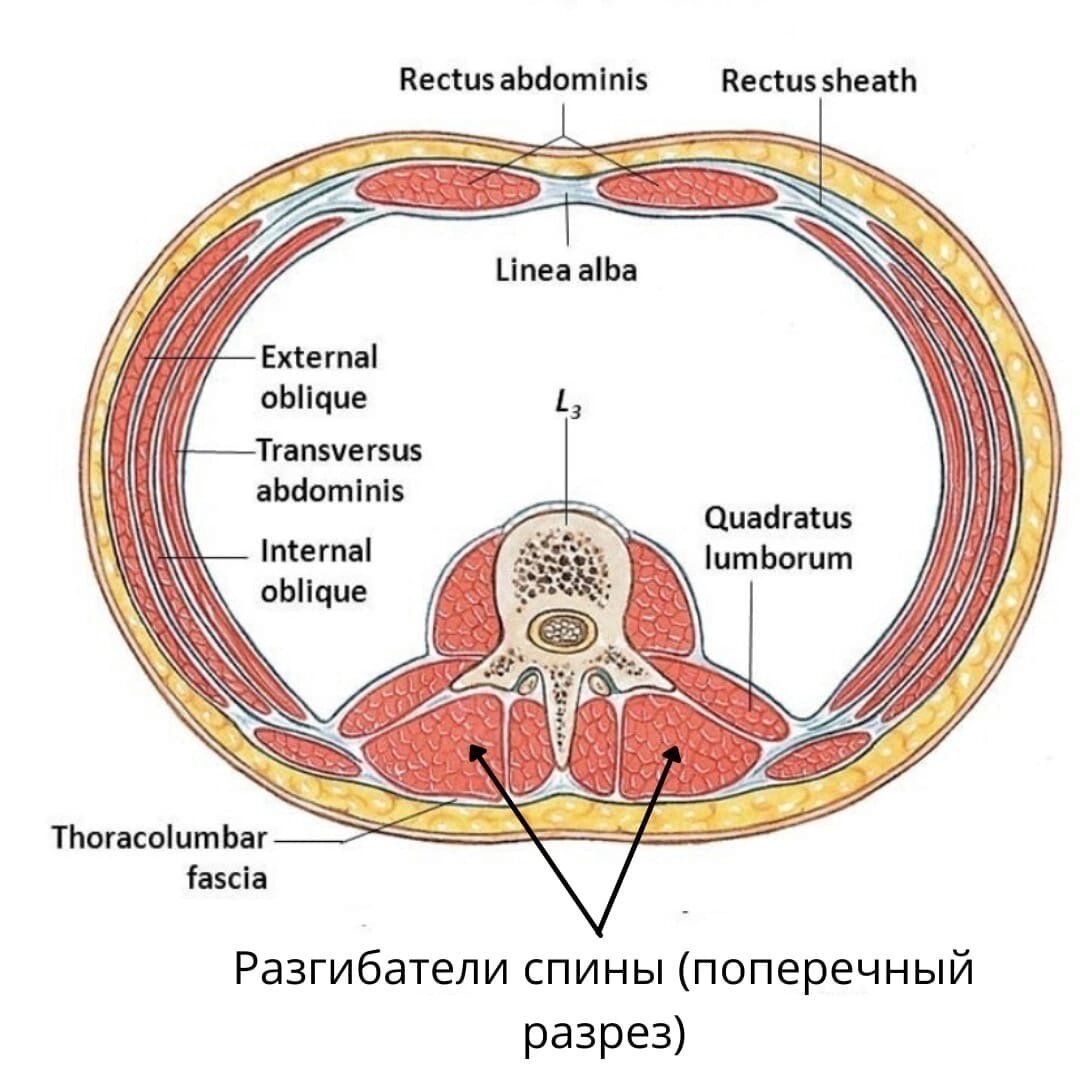

Анатомия диафрагмы и треугольника Бохдалека

Раздел: Визуальный дайджест